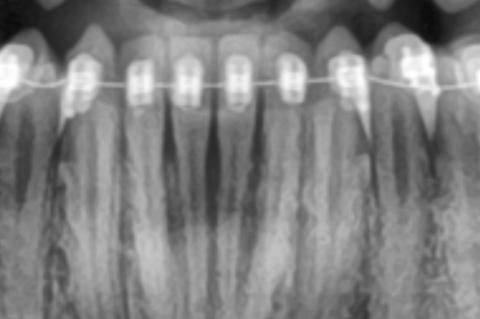

Bone Loss Around Front Teeth With Braces X-Ray Case

Bone Loss Around Front Teeth With Braces X-Ray Case Analysis

What Is Seen in This Case

The X-ray image shows the lower front teeth with orthodontic braces in place. The tooth roots are visible, but the bone level around the roots appears reduced and uneven. There are darker areas between and around the roots, suggesting loss of supporting bone rather than healthy, dense bone.

This finding is especially important in patients undergoing orthodontic treatment.

Professional Comment